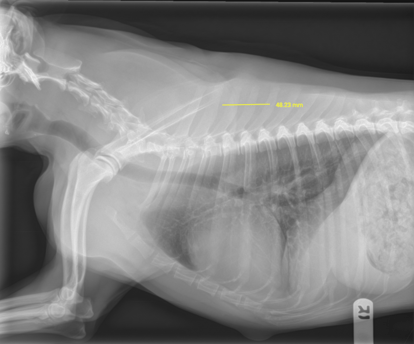

A DICOM file allows our radiologists to take a precise 48.23 mm measurement.

For example, in a DICOM image, our radiologists can use tools to accurately measure structures like a 48.23 mm mass—directly within the system (example below)